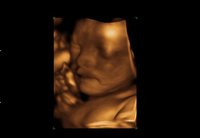

Se le extirpa un tumor a un bebé "a medio nacer", en pleno proceso de parto

NoticiasLas técnicas quirúrgicas están revolucionando nuestros conceptos de lo que es o no es posible. No es la primera vez que hablamos de la fetoscopia, en esta página. Estos días ha ocurrido algo relacionado con eso aunque no exactamente igual...